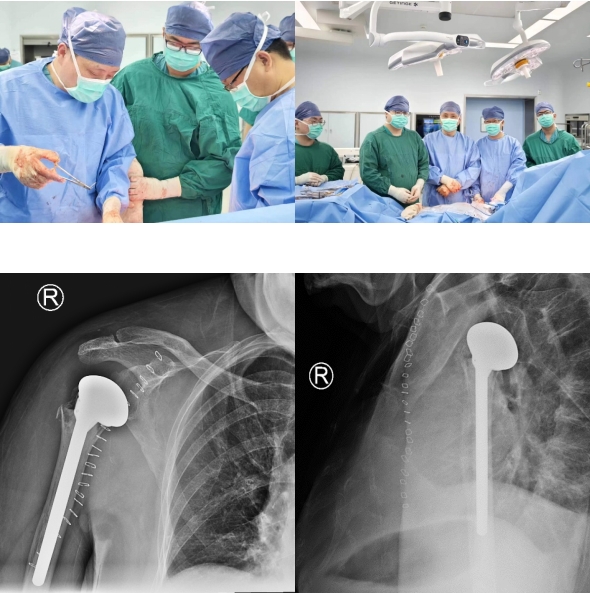

4月25日,苏州大学附属第四医院骨科杨小海主任治疗组顺利完成我院第一台肩关节置换手术,成功填补我院该项技术开展的空白。

手术方案制定后,经过缜密的术前准备,手术如期进行。整个手术过程仅持续了2个小时,杨小海主任团队顺利完成了我院骨科第一台肩关节置换手术,填补了苏大附四院骨科该术式开展的空缺。术后患者复查X片提示肩关节假体位置满意,手术获得成功。在佩戴支具固定1-2周后,申阿姨便可开始患肩的功能锻炼,申阿姨及其家人对此次治疗就医经过表示满意。